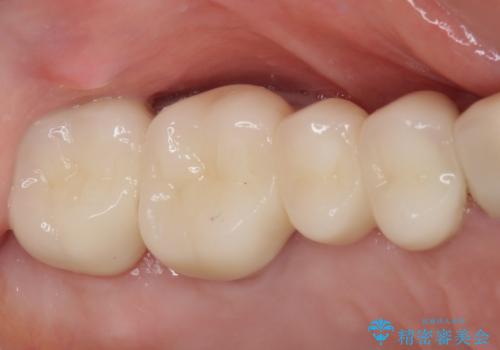

奥歯の歯槽骨が失われた 歯周外科処置後のセラミックブリッジ

処置後はオールセラミックブリッジにて補綴し、再発防止のために就寝時にナイトガード(マウスピース)を装着していただくこととしました。